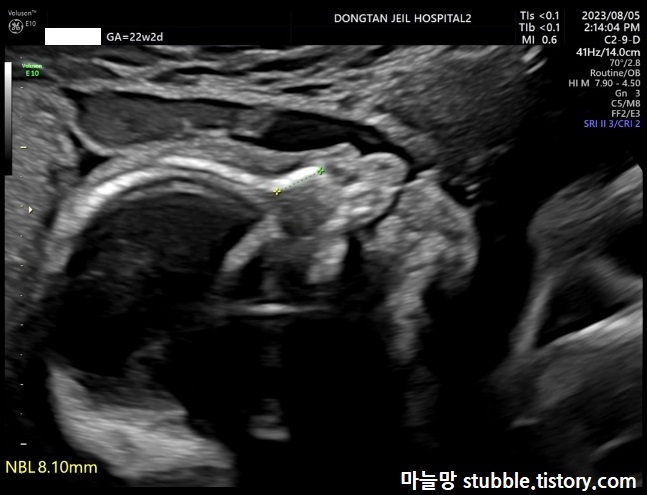

14. 코뼈의 존재 여부 및 길이 (NBL)

코뼈의 유무에 대해서는 12주 초음파에서도 봤었지만 이번에는 꽤 많이 성장한 코뼈를 볼 수 있었어요.